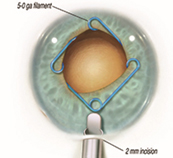

最近では白内障同時の極低侵襲緑内障手術 iStent手術(右)が保険診療で手術ができるように認定されました。

その他CTR手術(左)・瞳孔形成術・眼内レンズ入替術・裂孔閉鎖術・Add-onレンズ挿入術・眼内レンズ回転術など手術をいろいろなデバイスや術式で行っております。